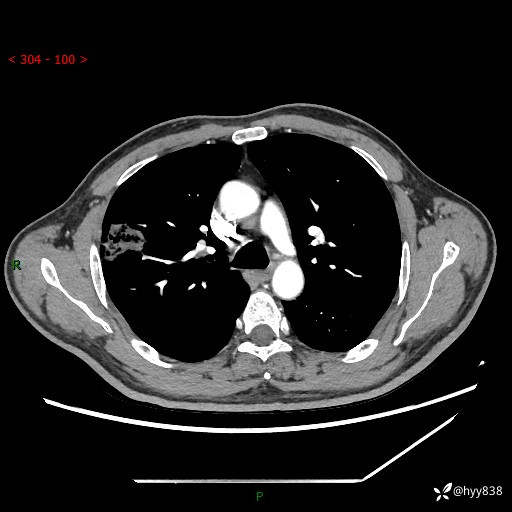

现病史:患者2天前体检完善胸部CT提示:右上肺团块影,炎症可能,肿瘤性病变不除外,冠状动脉钙化,无咳嗽、咳痰,无寒战发热,无恶心、呕吐等其他特殊不适,未予以特殊治疗,现为明确病变性质来我院就诊,门诊以“肺肿物性质待查”收入我科。 起病以来,患者精神、饮食、睡眠可,大小便正常,体力体重较前无明显变化。

胸部CT平扫+增强